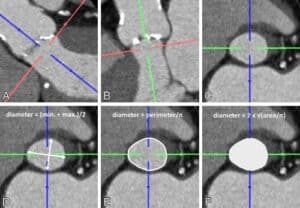

1. Medición del Anillo aórtico:

En primer lugar, hay que definir con gran precisión el tamaño del anillo aórtico, (esto permite seleccionar el tamaño de la prótesis aórtica percutánea) especialmente cuando es de morfología ovoide.

Tomografia Cardiaca y medición del anillo aortico